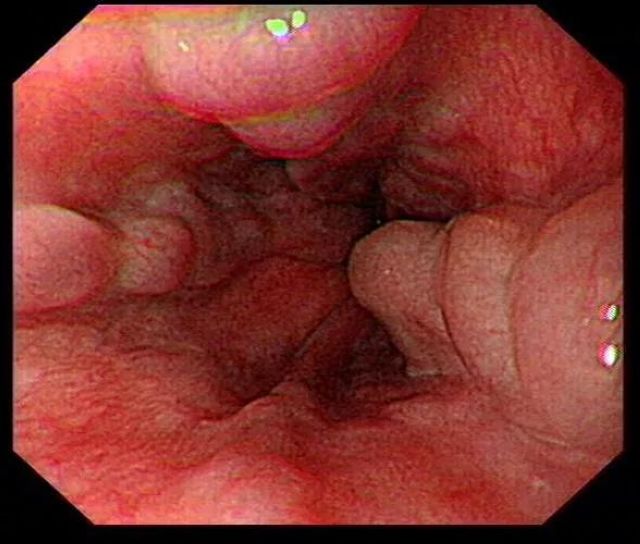

术前胃镜

唐女士既往患有慢性乙型肝炎后肝硬化(失代偿期)、食管胃底静脉曲张、消化道出血病史数年,曾经因反复消化道出血多次住院治疗。此次再次因“呕血、黑便3小时”入院于消化内科,诊断为上消化道出血、乙肝后肝硬化伴食管胃底静脉曲张破裂出血、失血性贫血、高血压等。